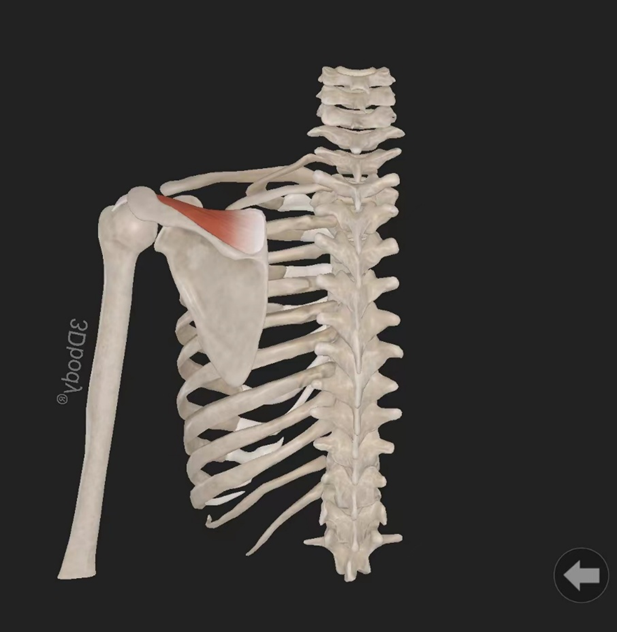

小圆肌:起自肩胛骨外侧缘背面,止于肱骨大结节下部。由腋神经(C5—7)支配。作用:使关节旋外。

冈上肌:起自冈上窝,穿过肩峰和喙肩韧带,止于肱骨大结节上部部。由肩胛上神经(C5—6)支配。作用:使肩关节外展。

冈下肌:起自冈下窝内,止于肱骨大结节中部。由腋神经(C5—7)支配。作用:使关节旋外。

肩胛下肌:起自肩胛下窝(肩胛骨前面),止于肱骨小结节。由肩胛下神经(C5—6)支配。作用:使肩关节旋内、内收。